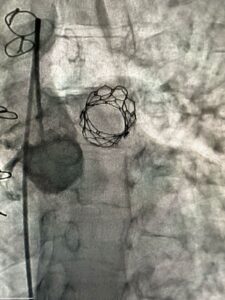

وقال الدكتور حسام عبدالغفار المتحدث الرسمي لوزارة الصحة والسكان، إنه من خلال دعم الدكتور خالد عبدالغفار، نائب رئيس مجلس الوزراء ووزير الصحة والسكان، للجهود المتواصلة التي تبذلها المؤسسة العلاجية لتطوير مستشفياتها والارتقاء بمستوى الرعاية الصحية المقدمة بأعلى مستويات الجودة والكفاءة، مع التركيز على التدريب المستمر للفرق الطبية على أحدث التقنيات والتدخلات الجراحية الدقيقة، نجح الفريق الطبي في زرع الصمام الرئوي داخل صمام نسيجي سابق، لمريض عمره 22 عاما، وهي العملية الأولى من نوعها، التي يتم خلالها وضع صمام، داخل صمام نسيجي سابق، وتركيبه جراحيًا، وهي من التدخلات الدقيقة وشديدة التعقيد.